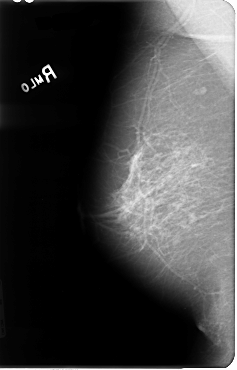

B_3046_1.RIGHT_MLO

RIGHT_MLO LINES 4800 PIXELS_PER_LINE 3072 BITS_PER_PIXEL 12 RESOLUTION 50 NON_OVERLAY